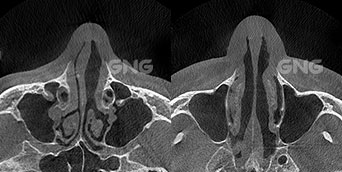

⭐ 비중격만곡증, 비밸브 협착 20대 남자 환자분의 코막힘 수술 케이스왼쪽 코막힘을 심하게 앓고 계셔서 내원하셨습니다.왼쪽 상방 부분에는 비밸브가 위치하고 있는데요.비중격과 왼쪽 측벽 사이의 공간이아예 없는 완전 협착 상태였습니다.비밸브 교정술을 통해가운데로 기둥을 옮겨 주어비밸브 쪽의 공간과 양쪽 비강이비슷해지게 맞춰주었습니다. 뒤쪽에서 본 CT에서도비중격 뼈가 . . .